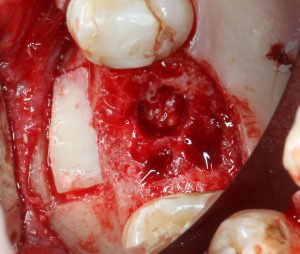

Кортикальная фреза погружается строго до отметки (см выше). В нашем клиническом случае (с синуслифтингом) это особенно важно, чтобы имплантат не улетел в субантральное пространство. Таким образом получаем лунку, полностью конгруэнтную будущему имплантату. Это очень-очень важно:

Пришло время вернуться к синуслифтингу и заполнить сформированное ранее субантральное пространство графтом (Geistlich Bio-Oss Pen):

запечатываем заполненное субантральное пространство:

Как это правильно сделать, читайте здесь>>, здесь>> и здесь>>.

Приступаем к установке имплантата.

Если лунка подготовлена правильно, то имплантат проваливается в неё почти полностью:

и докручивается до правильного положения несколькими оборотами.